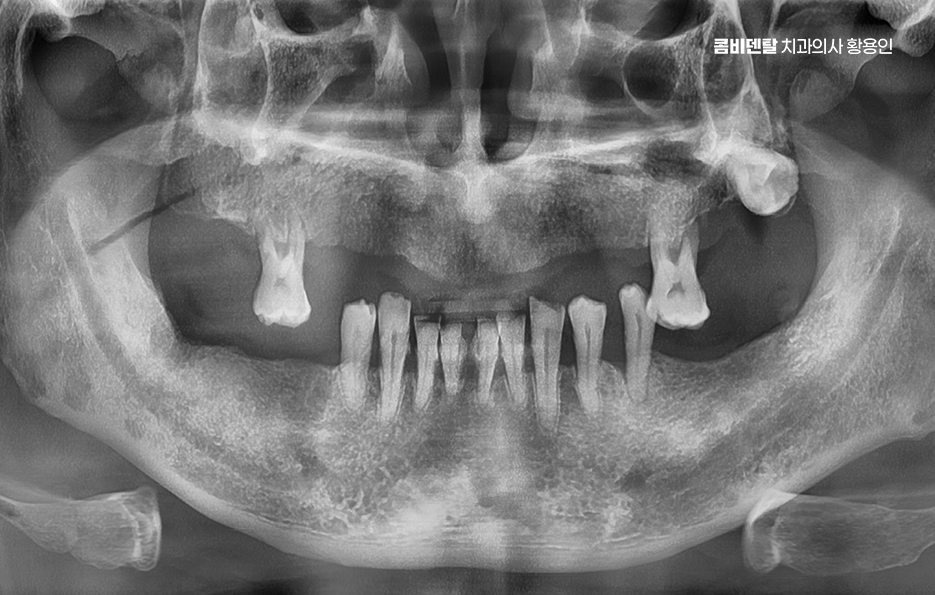

윗니가 하나둘 빠지기 시작했을 때까지만 해도 이렇게까지 될 줄은 몰랐어요. 처음엔 단순히 오래된 충치가 더 이상 버티지 못해서 빠졌다고 생각했어요 그런데 어느 순간부터 그 ‘하나둘’이 점점 늘어나더니, 이제는 위쪽 치아 대부분이 사라져 버렸고, 윗니가 비어 있는 모습이 너무 낯설게 느껴졌어요. 그때는 몰랐어요. 치아는 하나 빠지면 주변까지 영향을 받고, 잇몸뼈는 생각보다 빨리 무너질 수 있다는 것을 말이에요 임시 틀니를 잠시 사용하고 있는데, 그 불편함은 말로 다 설명하기 어려울 정도였어요

이처럼 과거에는 치아를 잃는 것이 자연스러운 노화로 받아 들이기도 했고 틀니를 하는 경우가 많았지만 요즘은 기대수명의 증가로 인해 노인 분들의 전체임플란트 치료 사례가 크게 늘고 있으며 틀니 보다는 임플란트 쪽으로 알아보는 경우가 확실히 늘고 있는데요

윗니 전체를 임플란트로 치료해야 하는 상황이 생겼다는 건 단순히 몇 개 치아를 잃은 게 아니라, 치아 기능 전체가 무너졌다는 의미이며 이런 경우에는 단순히 개별 치아 하나하나를 심는 방식으로 접근하면 비용도 고가이고 비효율적이며 구조적으로도 안정성이 떨어질 수 있기 때문에 처음부터 전체적인 구강 구조를 고려한 통합적인 치료 계획이 필요할 수 있어요

보통 윗니 전체 임플란트를 계획할 때 먼저 해야 하는 건 CT 촬영을 통한 잇몸 뼈 상태 진단으로 윗니는 아래보다 뼈가 더 얇고, 특히 어금니 쪽에는 상악동이라는 빈 공간이 있기 때문에, 임플란트를 심을 수 있는 잇몸 뼈의 양이 부족한 경우가 많다보니 이런 경우에는 단순히 임플란트를 심을 수 없기 때문에 상악동 거상술이라는 수술이 필요하게 되는 경우도 있는데요

이 수술은 상악동 점막을 들어 올리고 그 아래에 뼈이식 재료를 넣어서 임플란트가 들어갈 수 있는 충분한 공간을 만들어주는 방식이며 그 외에도 잇몸 뼈 상태나 전신 건강, 흡연 여부 같은 조건에 따라 구체적인 치료 방법이 달라지기 때문에 이처럼 윗니 전체 임플란트의 경우 기본적으로 임플란트를 지지할 수 있는 잇몸 뼈가 충분한지 정확한 진단이 치료의 시작점이 되고 있어요